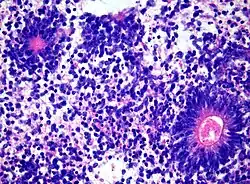

Charakteristisch sind zahlreiche sogenannte ependymoblastomatöse Rosetten. [Hämatoxylin-Eosin-Färbung]

Neuropathologisch ist für den Tumor die Ausbildung mehrreihiger Rosetten, die als ependymoblastomatöse Rosetten bezeichnet werden, charakteristisch. Angesichts der Beobachtung, dass ependymoblastomatöse Rosetten auch bei anderen embryonalen Tumoren vorkommen können, war die Bedeutung des Ependymoblastoms als eigenständige Entität bereits früh umstritten.[1]